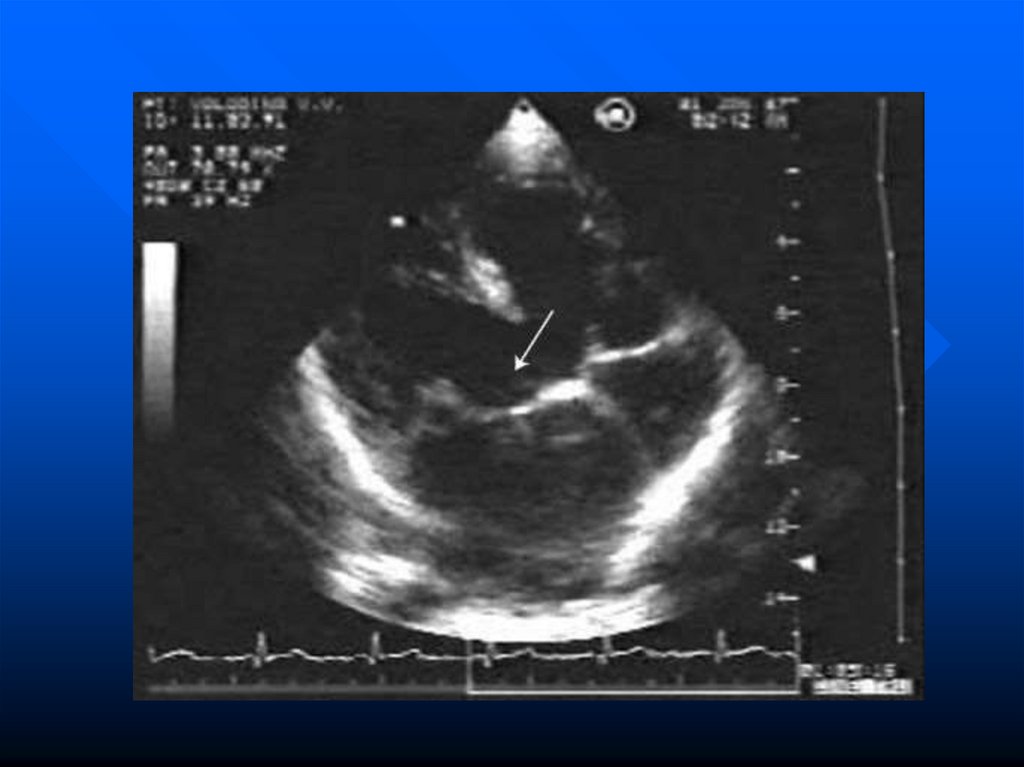

формируется

клапанный

аппарат.